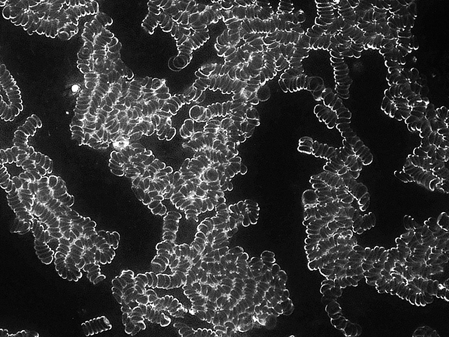

Telefonat ohne Schutz-Transmitter

Nach 1o-minütigem Telefonat verklumpen die rote Blutkörperchen  miteinander, da sie sich nicht mehr abstoßen.

Durch die Verklumpung treten eine Einschränkung der Funktionsfähigkeit bzw. der Mobilität der roten Blutkörperchen ein. Die Folgen sind: Durchblutungsstörungen, Stauungen sowie eine Sauerstoffunterversorgung der Körperzellen und eine Übersäuerung des Bindegewebes.